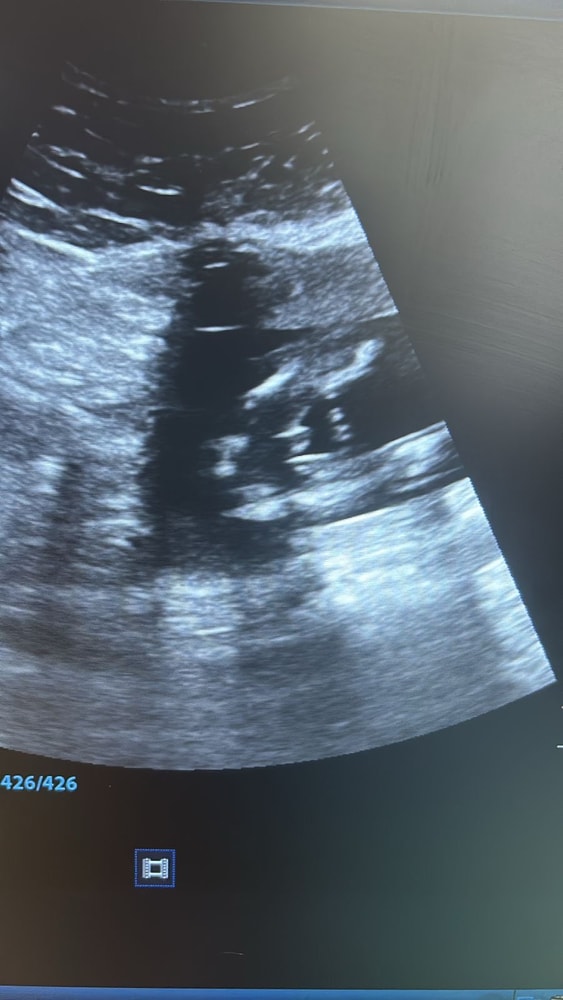

на первом узи в 12 недель врач сказал у вас девочка (но конечно верить не могу на первом узи, так как в 12году с сыном до 3 скрининга говорила девочка, а со вторым в принципе все время говорили мальчик, один раз не поняли кто 😅)

на втором узи в 20 недель врач дал конверт в котором было написан